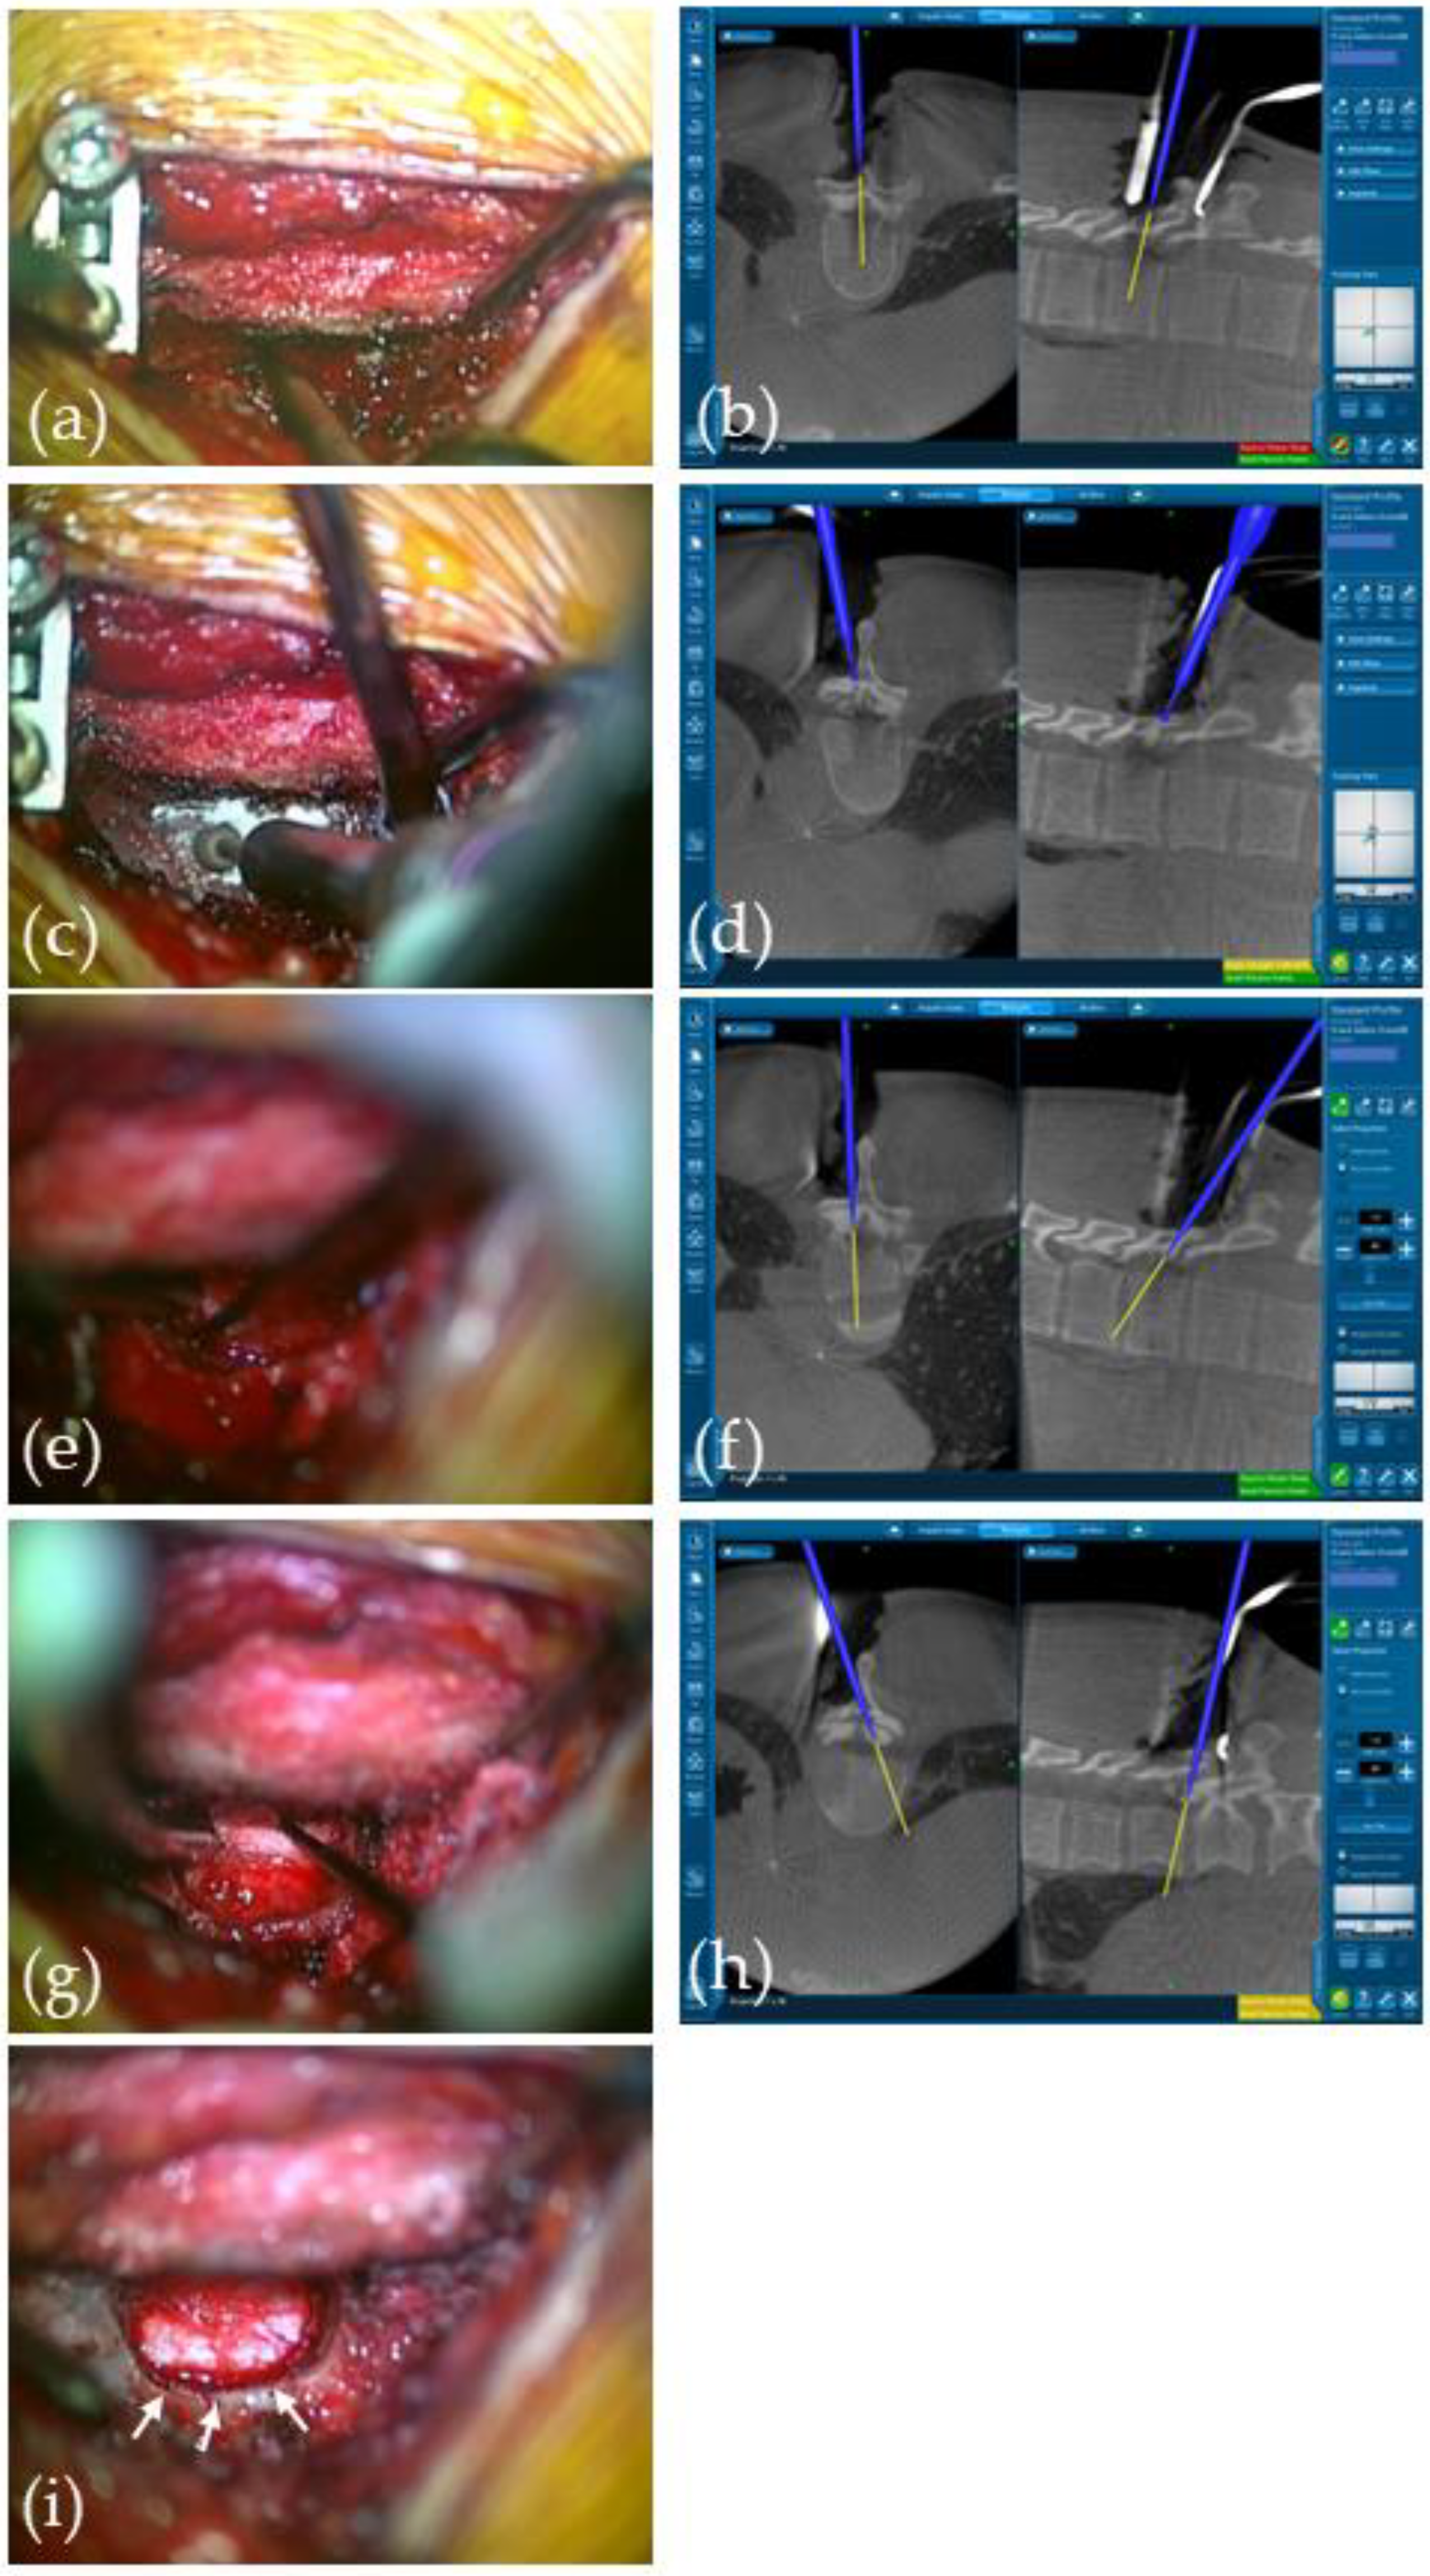

2.2. Surgical Technique